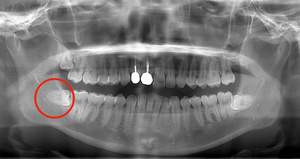

抜くのが簡単で、痛みが出にくいケースは、真っ直ぐはえている上顎の親知らずです。上顎は下顎よりも骨が柔らかく、かつ根が真っ直ぐになっていることが多いためです。そのため抜くのが簡単な傾向にあります。

下顎でもまっすぐはえている場合は簡単に抜け、痛みが出にくいケースもあります。

抜歯が簡単で、痛みが出にくい真っ直ぐ生えている親知らず症例のレントゲン写真